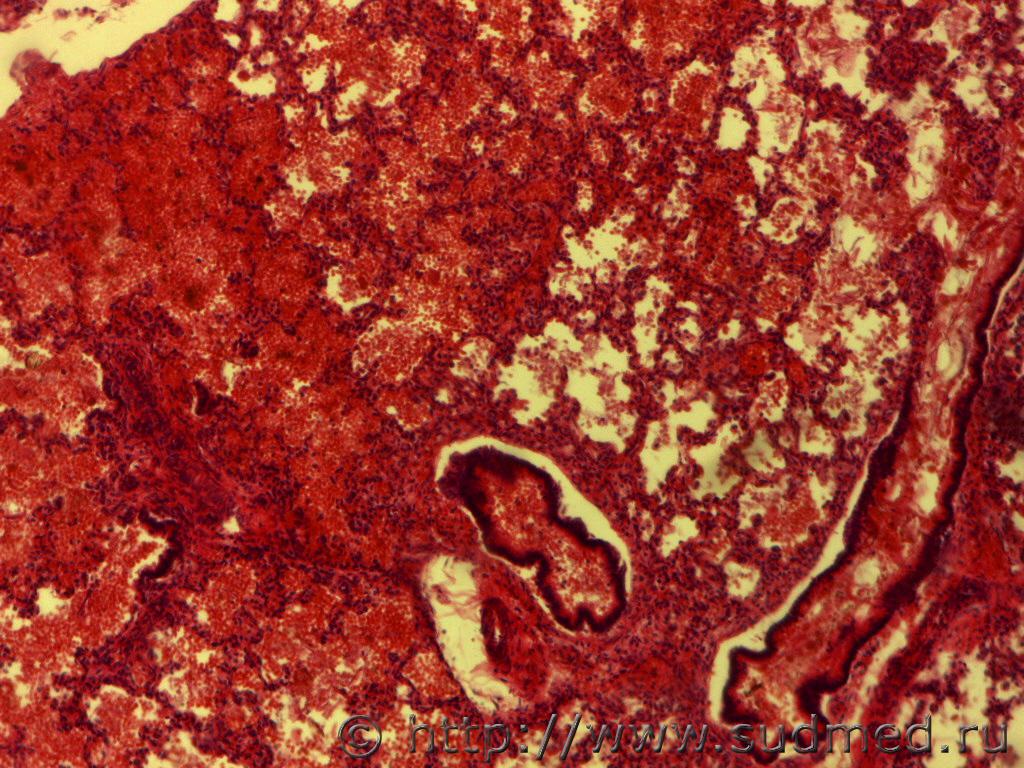

Здравствуйте, уважаемые эксперты! я начинающий гистолог, помогите разобраться с легкими - дышавшие или нет? Девушка 1986г.р. рожает первого ребенка, ребенок родился мертворожденным, беременность проходила хорошо, роды в срок, жалоба на врача, что во время схваток к ней долгое время никто не подходил. Танатолог берет 4 кусочка легких, в\д,ср\д левого легкого, ср\д, н\д правого легкого, легочные пробы - легкие в воде тонут. Со слов врачей ребенка пытались реанимировать, никаких записей это подтверждающих нет. То что там аспирация околоплодными водами очевидно, меня смущает полное расправление всех альвеол, даже эмфизема.

фото прилагаю

(6-е и 8-е фото окраска по Ван Гизону)

1.Расправленные в результате самостоятельного дыхания терминальные дыхательные пути имеют чёткие очертания без признаков острой эмфиземы - такой картинки не вижу.

2.При искусственном дыхании расправляются некоторые альвеолы,но полного расправления лёгких не наблюдается.Характерным считается проникновение воздуха в верхние доли,в том числе и верхушки лёгких,по передненижним краевым зонам и по междолевым поверхностям.Главным признаком искусственной вентиляции лёгких является острая эмфизема с нарушением целости респираторной паренхимы.Эмфизематозные изменения имеют характер структурных нарушений в виде разрывов межальвеолярных перегородок с образованием эмфизематозных очагов,окружённых участками дистелектаза.

3.Мне представляется,что на фото лёгкие после искусственной вентиляции.

Добрый день! наблюдается неполное расправление просвета альвеол, альвеолярные перегородки извилистые, широкие междольковые прослойки, просвет альвеол местами выполнен свежей кровью, с примесями десквамированных альвеолоцитов, встречаются овальные, кубические альвеолоциты, местами и в просвете отдельных бронхиол имеется примеси свежих эритроцитов. В просвете альвеол единичные фрагменты роговых чешуек( в присланных Вами микрофото), которые не может быть признаком массивной аспирации, т.к. внутриутробно в норме до бифрукации в просвете трахее бывает околоплодные воды. Участков ателектаза и острых очагов эмфиземы не видно в микрофото.

Мое предварительное мнение по присланным микрофото Респираторный дистресс-синдром новорожденных. Тонут легкие и при кровоизлиянии в респираторные отделы легких.